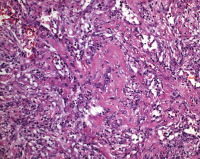

Lipidpneumonie - EVALI

Abbildung 4: Lipidpneumonie bei EVALI, transbronchiale Biopsie (H & E, X 400)

Keywords: EVALIHistologisches PräparatLipidpneumonie